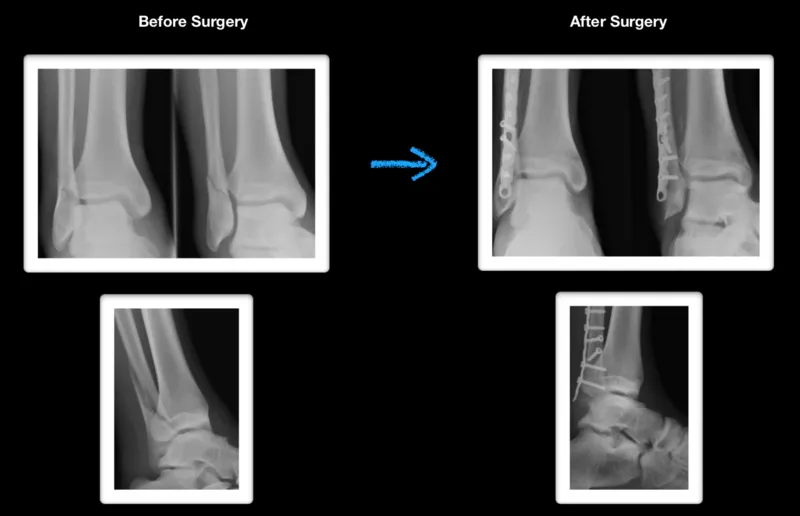

From www.hopkinsmedicine.org

Tibia/Fibula Fracture Open Reduction and Internal Fixation Johns Fibula Fracture Cast Time A forceful impact, such as landing after a high jump or any impact to the outer aspect of the leg, can cause a fracture. Most of the time, fibula fractures happen near the ankle joint. It can also happen when there’s more. If you need surgery or your fibula was displaced, it may be around 6 months before your pain. Fibula Fracture Cast Time.

Tibia and Fibula Fractures Johns Hopkins Medicine Fibula Fracture Cast Time There are lots of factors that can affect how long it takes your. Generally speaking, it can take a few weeks to several months. Repetitive stress fractures are also common. If you need surgery or your fibula was displaced, it may be around 6 months before your pain and swelling resolve. A forceful impact, such as landing after a high. Fibula Fracture Cast Time.